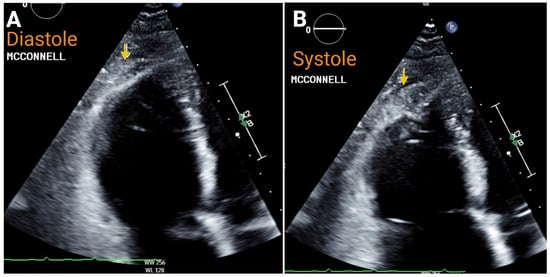

7.1. Acute Right-Sided Heart Failure

- McConnell, M.V.; Solomon, S.D.; Rayan, M.E.; Come, P.C.; Goldhaber, S.Z.; Lee, R.T. Regional right ventricular dysfunction detected by echocardiography in acute pulmonary embolism. Am. J. Cardiol. 1996, 78, 469–473. [Google Scholar] [CrossRef] [PubMed]